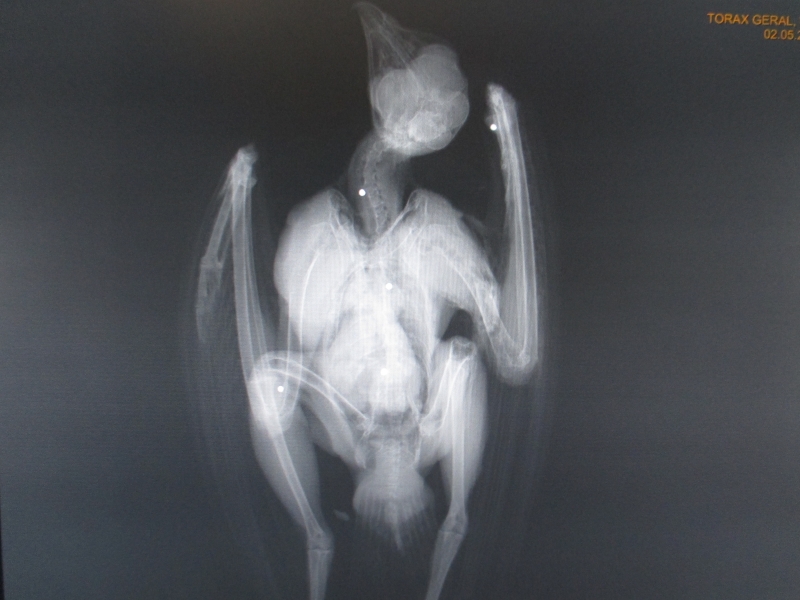

O dia-a-dia no centro é muito preenchido. Diariamente, a alimentação e o tratamento de cada animal em recuperação são preparados e ajustados à evolução do caso clínico. Os animais que chegam ao centro são avaliados clinicamente, a fim de se descobrir a causa da entrada e estabelecer um plano de diagnóstico e tratamento. Para além de tarefas como a realização de radiografias ou necropsias e a análise de fezes dos animais, é necessário garantir a limpeza dos materiais e espaços utilizados e das instalações onde recuperam os animais. Existem muitas outras atividades que fazem parte do quotidiano do centro, como a gestão do biotério de roedores, estudos e projetos nas áreas de medicina-veterinária e biologia, a manutenção das instalações e – o melhor de tudo – a devolução à natureza dos animais que foi possível recuperar.

Ainda que as principais ameaças variem consoante a altura do ano são quase exclusivamente antropogénicas. Por exemplo, três dos animais atualmente em recuperação no CERAS foram vítimas de tiro (um bufo-real, uma garça-branca-grande e uma águia-de-asa-redonda. Disparar sobre espécies protegidas é ilegal e havíamos notado um decréscimo de casos nos últimos anos, mas esta época venatória os números voltaram a subir e abarcando uma grande variedade de espécies. Outra das principais ameaças é a eletrocussão nas linhas elétricas. O prognóstico nestes casos é muito mau e a maioria das aves não resiste ou fica irrecuperável, como foi o caso da Aloé há vários anos e de uma águia-calçada o ano passado, que foi transferida para um parque biológico. O cativeiro ilegal de espécies protegidas continua a ser uma das principais causas de entrada nos centros de recuperação, bem como as colisões, seja com estruturas fixas (linhas, cercas, edifícios) ou móveis (atropelamentos).